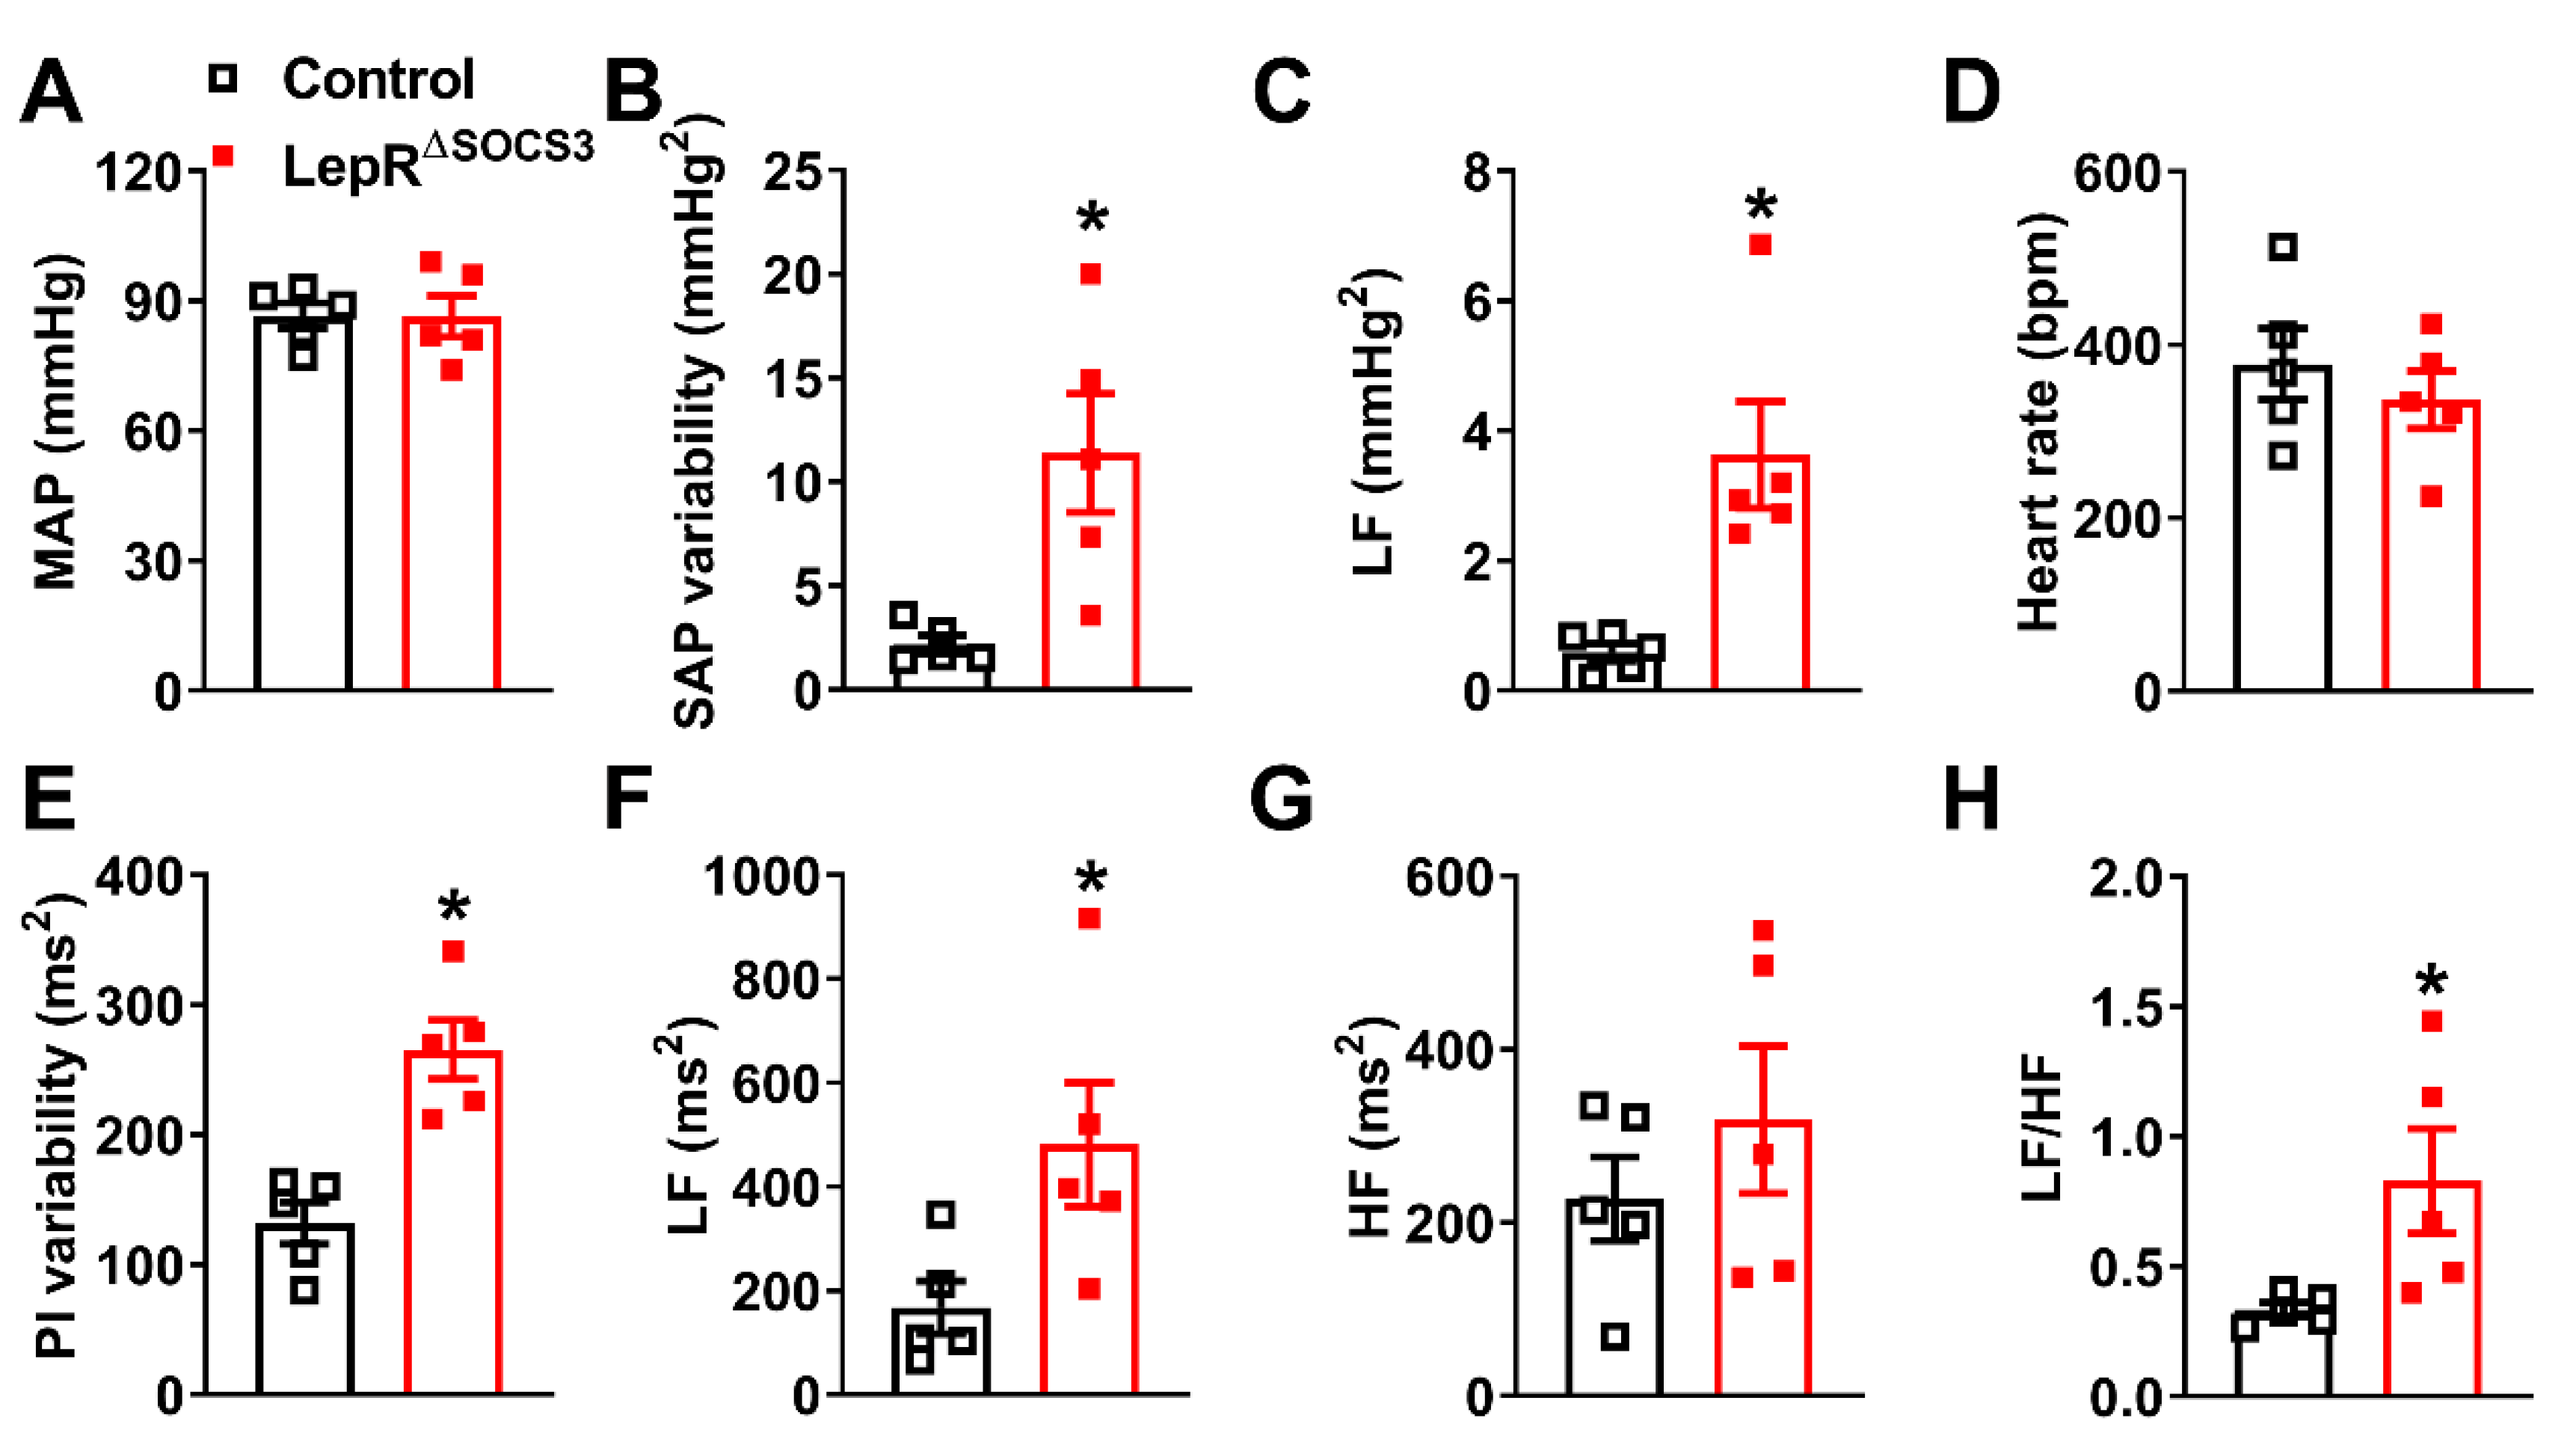

2.3. Cardiac Abnormalities and Decreased Survival Rate in Aging LepR∆SOCS3 Mice

4.7. Hemodynamic Recordings and Spectral Analysis